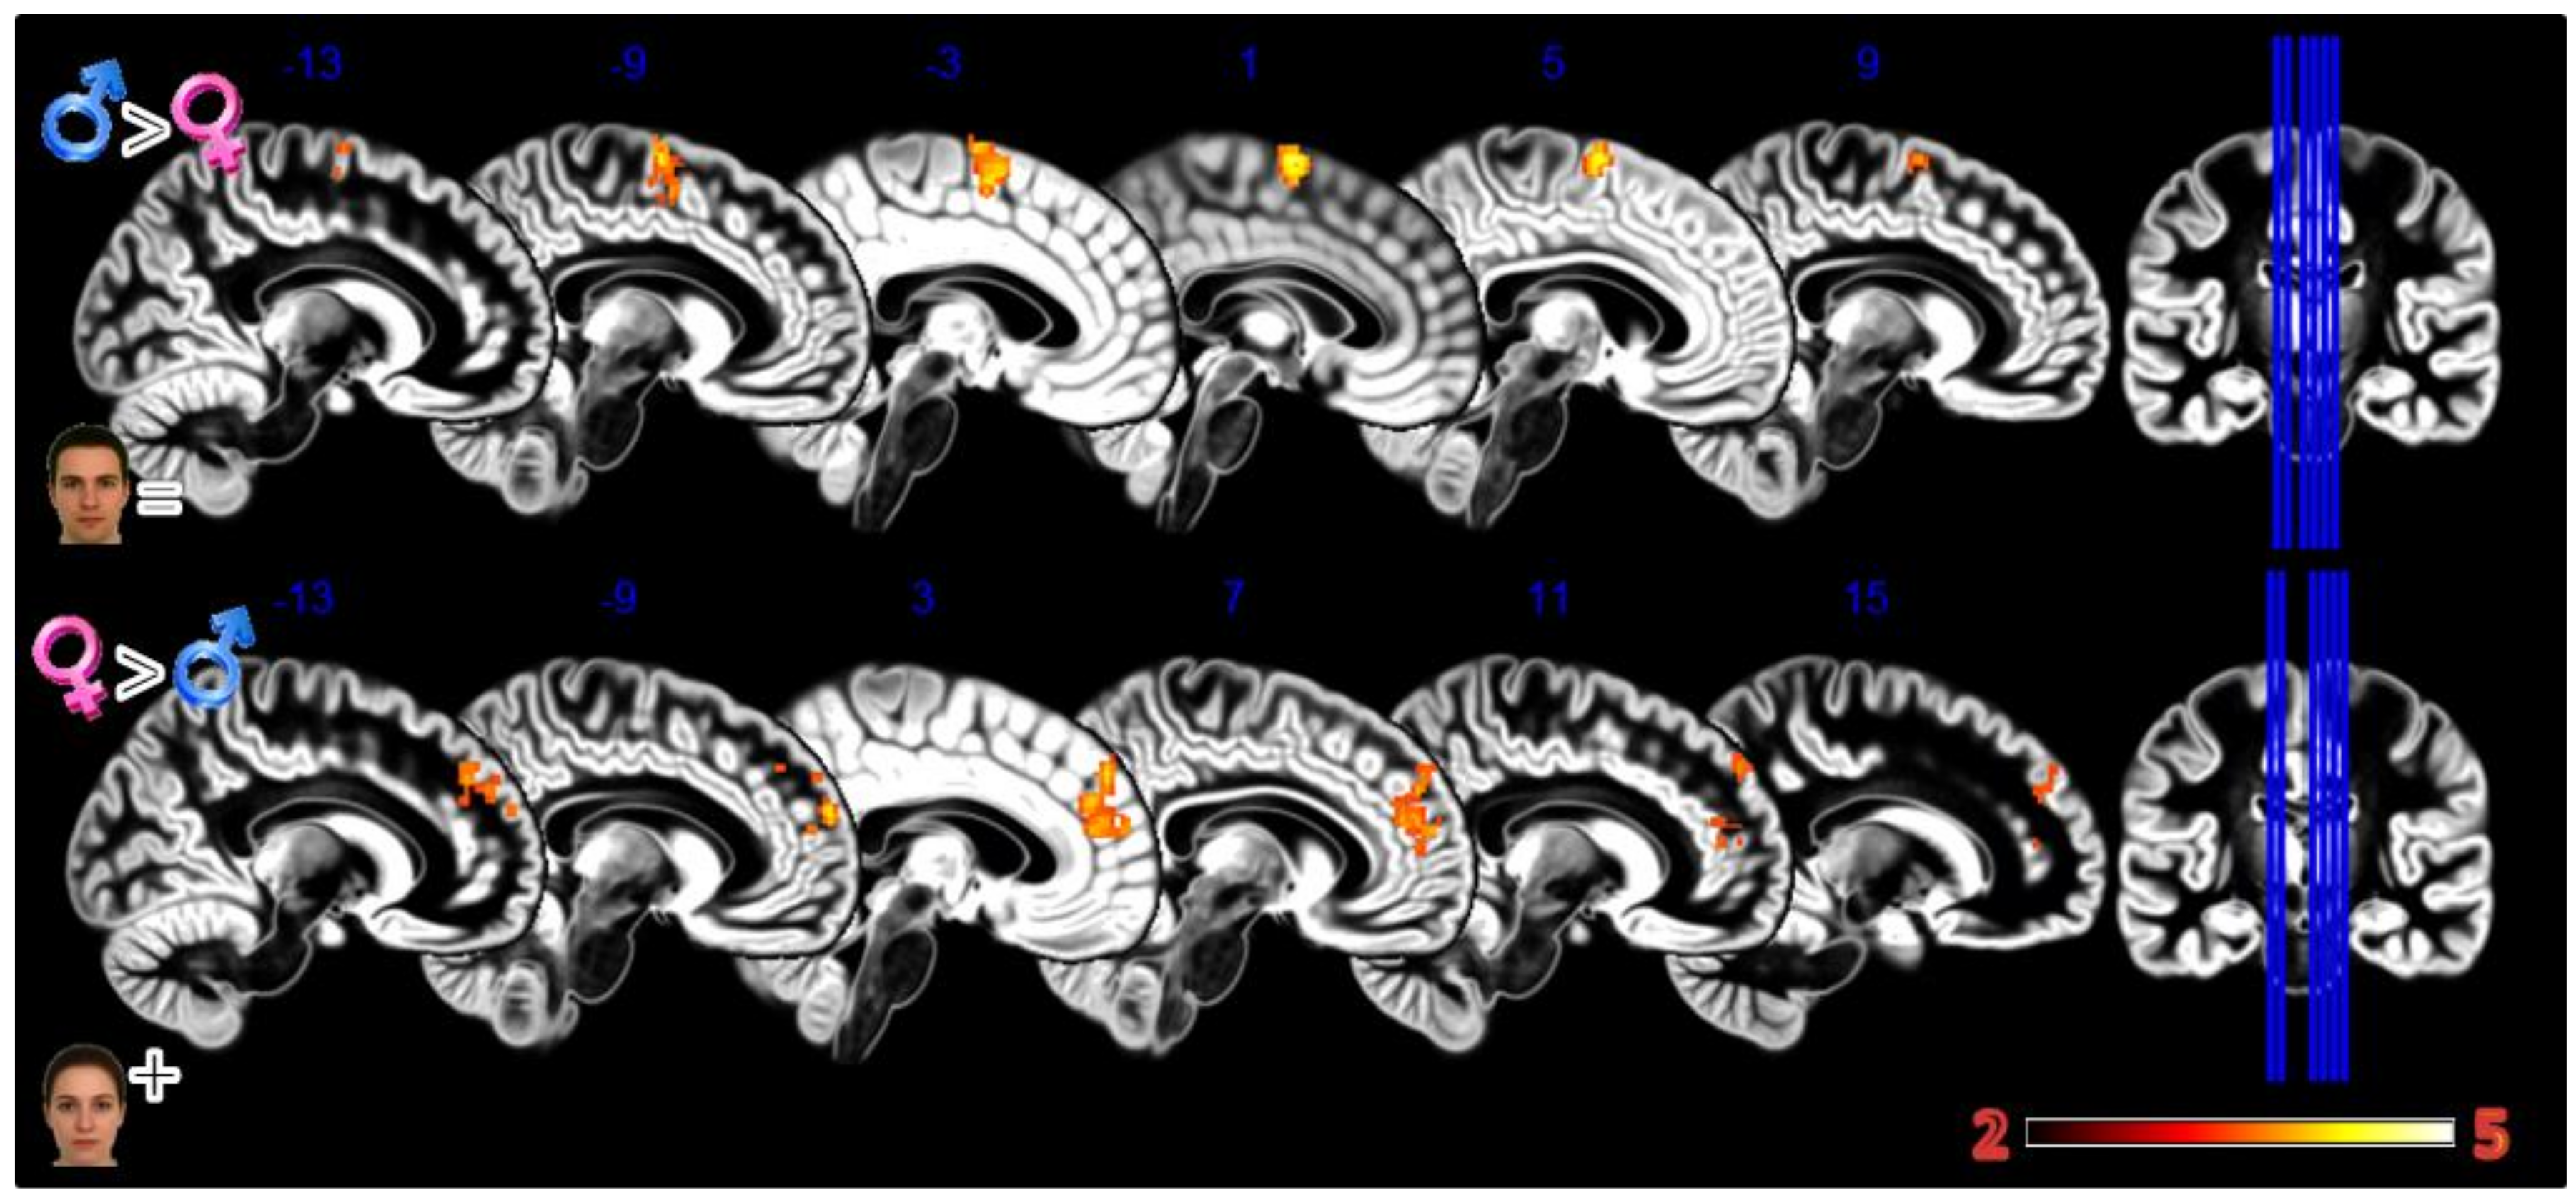

In the first experiment, Body Projection (Figure 3, Table 1), the male group activated more the bilateral thalamus when looking at sex congruent body images; the female group activated more the middle and inferior temporal gyrus when looking at sex congruent stimuli and the frontal superior medial cortex and bilaterally the more anterior and lateral portions of the precentral cortex when looking at androgynous body images.

Figure 3.

Group differences for the Body Projection experiment. First row Males greater than Females for male bodies, second row Females greater than Males for female bodies, and third row Females greater than Males for asexual bodies. In red significant clusters (p corr < 0.05) on a gray matter ICBM brain template, neurological convention, color scale in the bar maps for Z scores. In blue MNI coordinates in mm, and lines to show the slice positions on the orthogonal projections (right side of the figure).